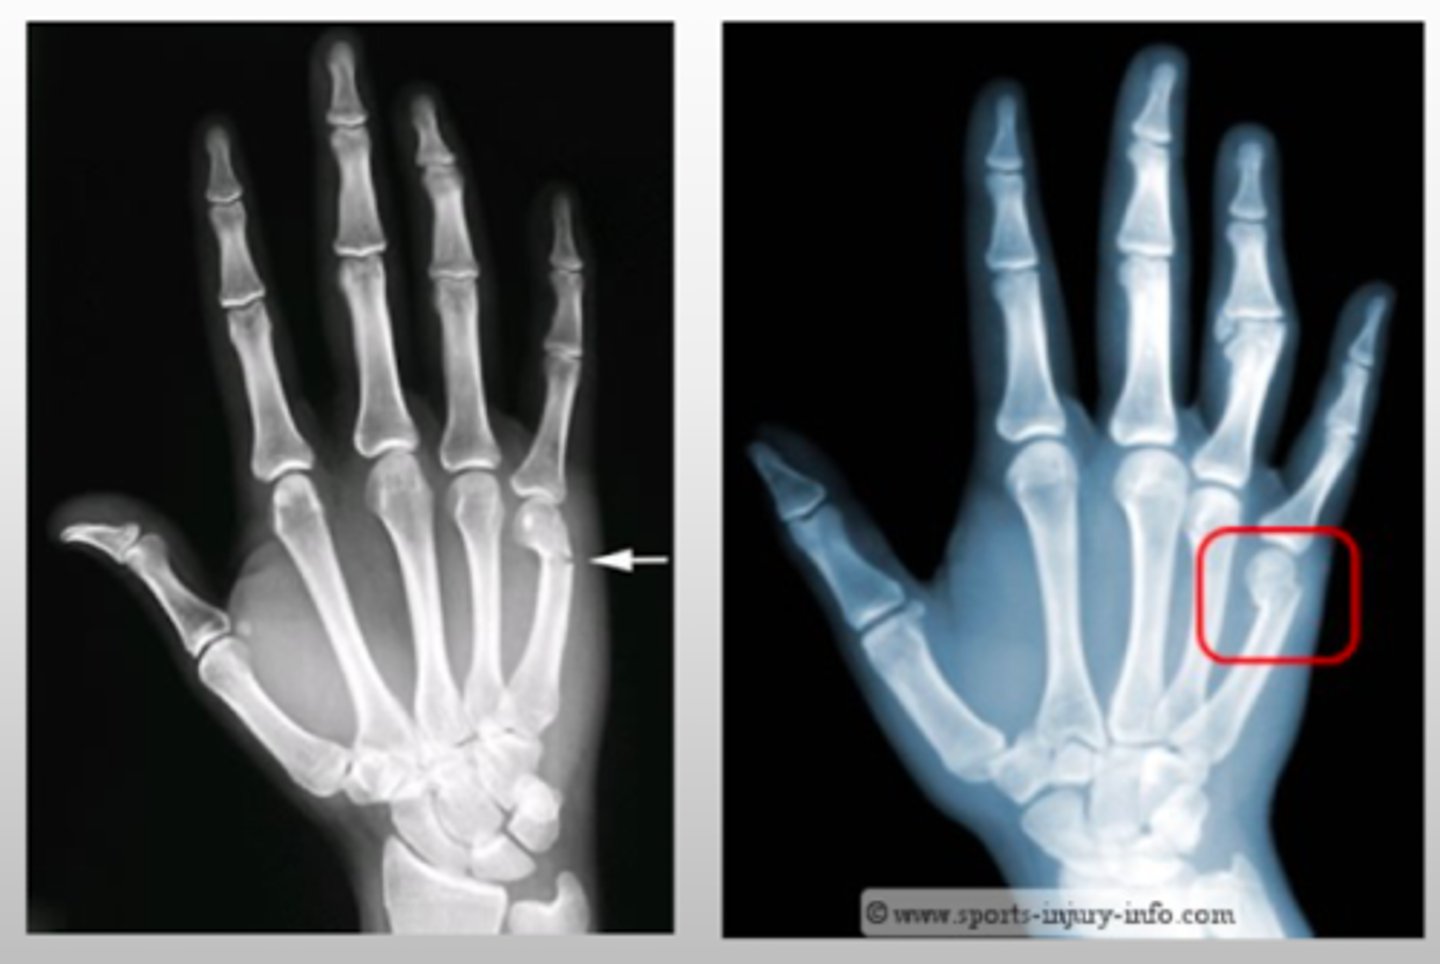

What type of fracture results from injury to the distal metacarpal neck?

Boxer's fracture

- will typically have a h/o punching an object

If a patient with a Boxer's fracture has a volar angulation is >25-30 degrees, what treatment is recommended?

reduction/splinting

- if >40 → surgery